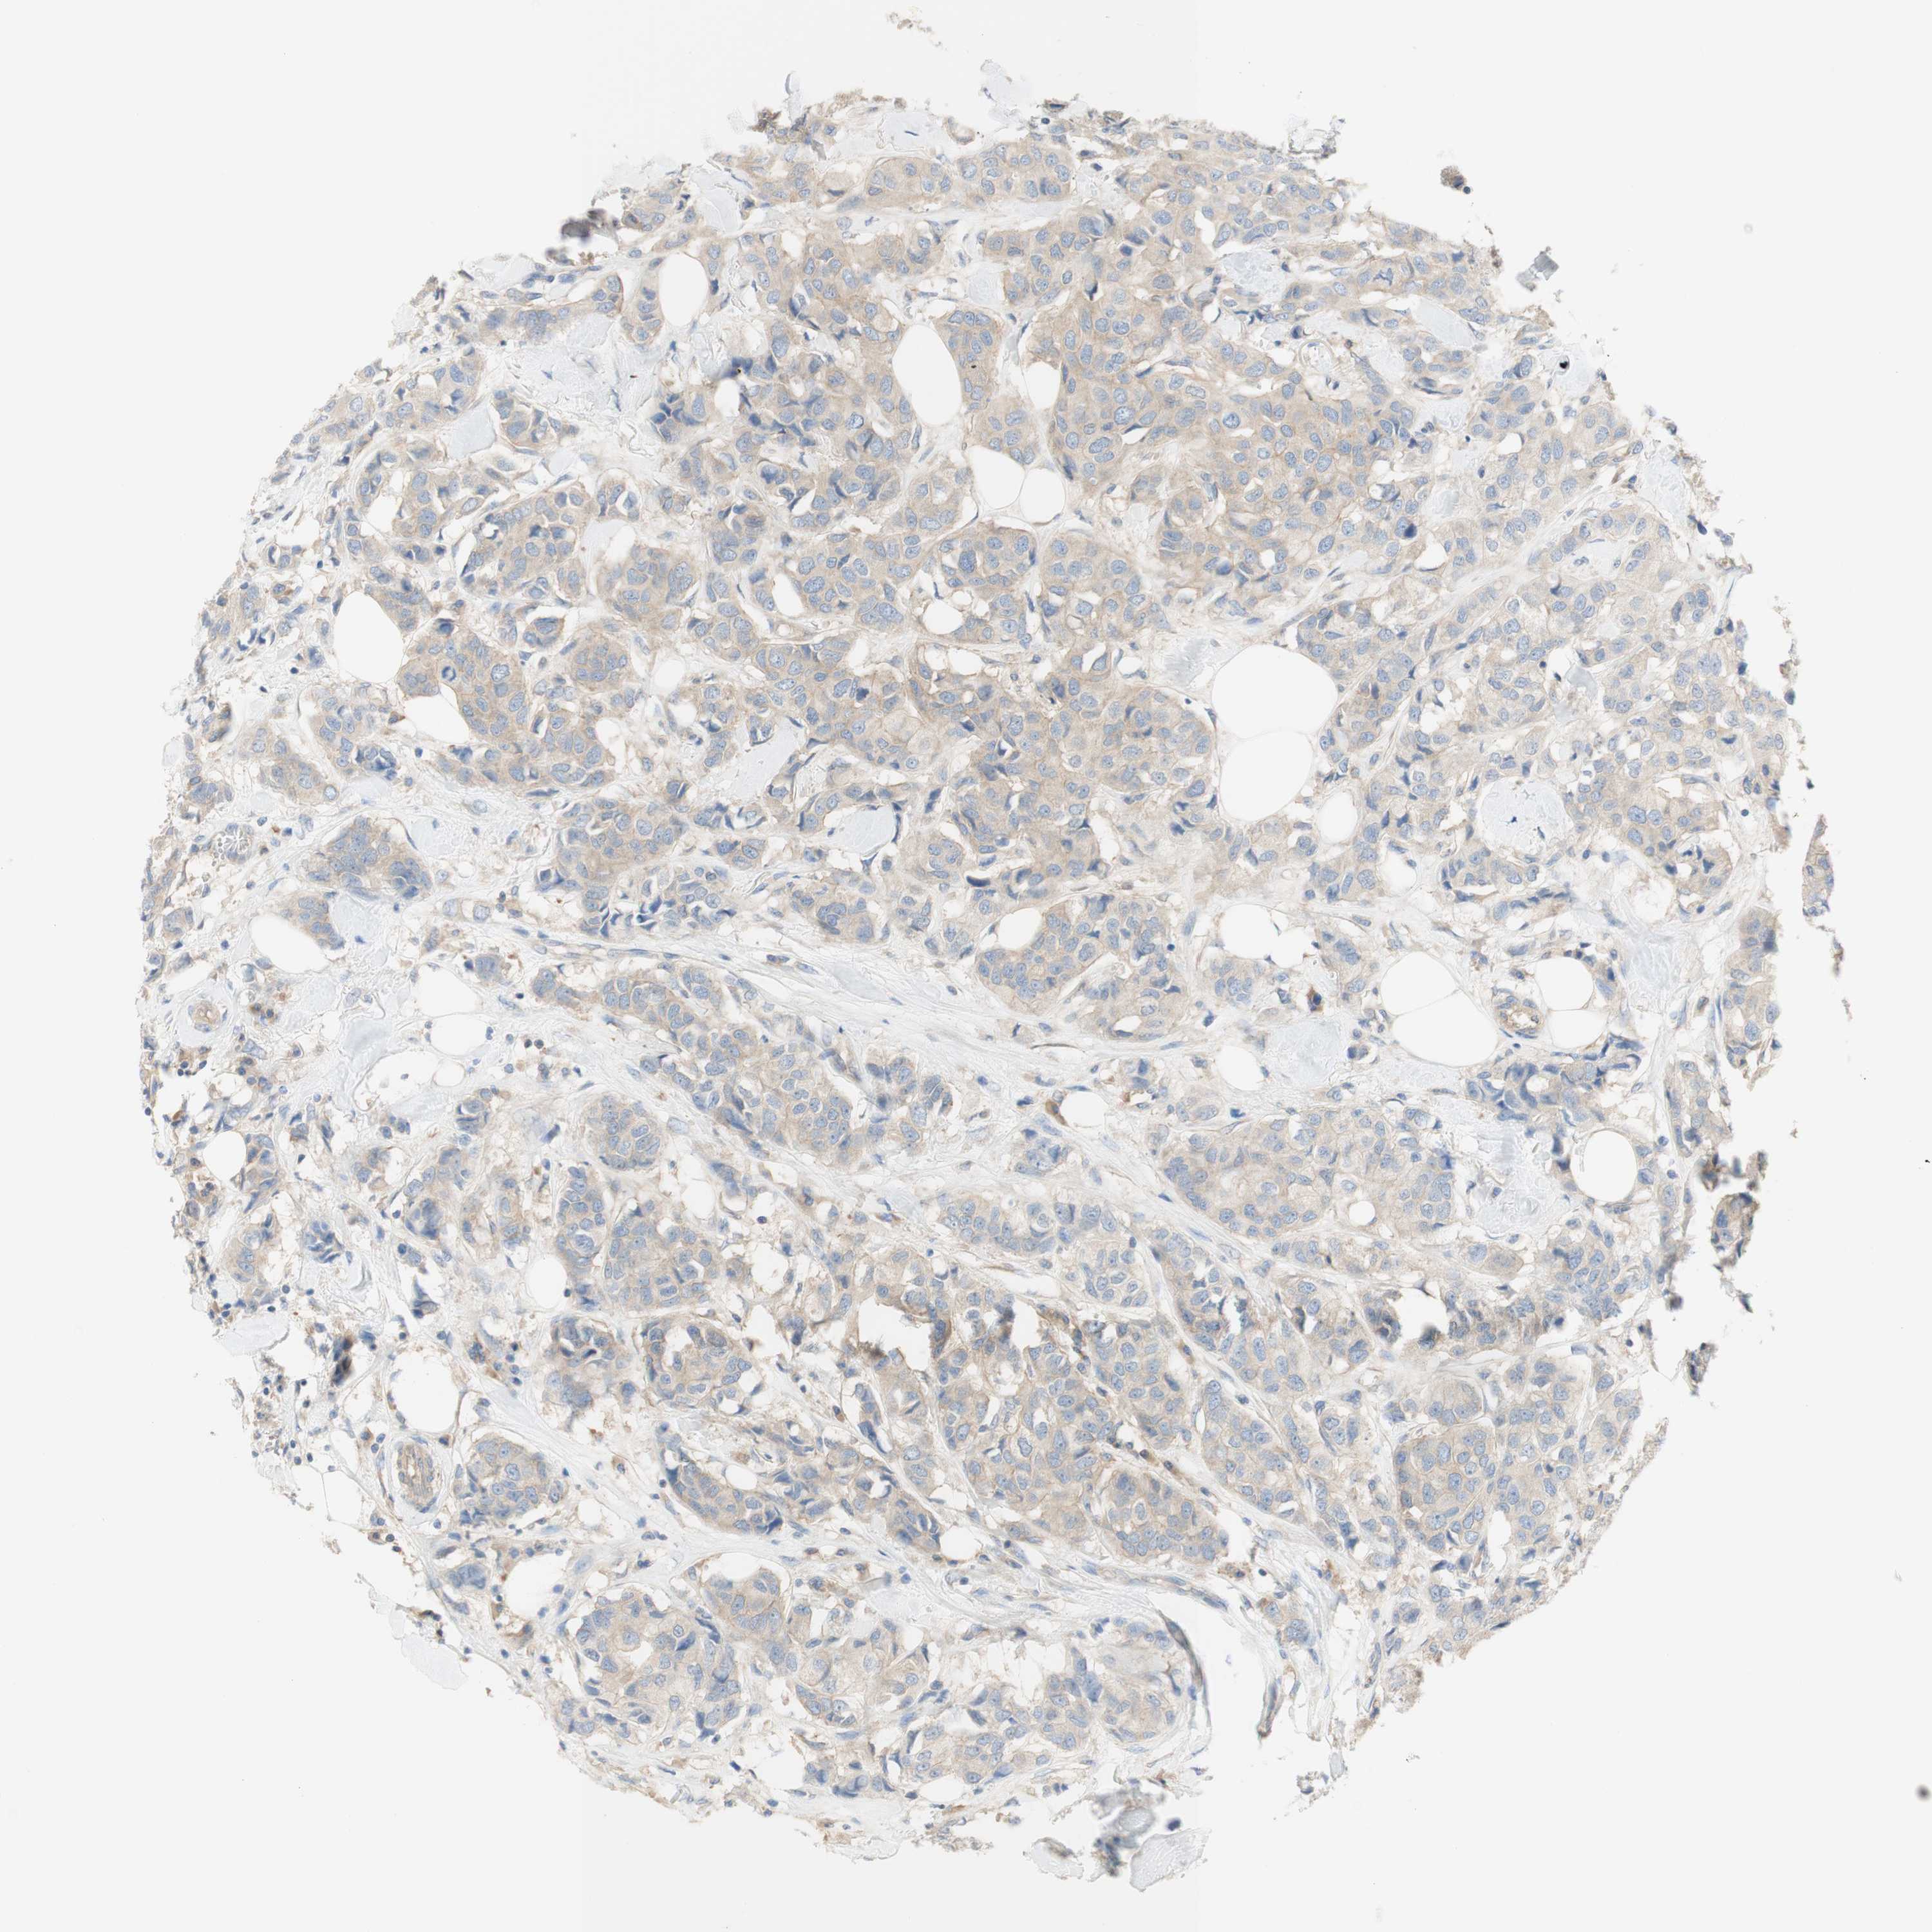

CANCER BREAST CANCER Show tissue menu

BRCA TCGA BRCA VALIDATION PROTEIN EXPRESSION